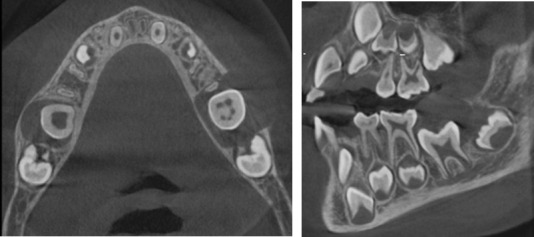

Dentigerous cysts are a common cystic pathology that develop between the first and third decade of life and are mainly associated with impacted or erupted mandibular third molars followed by maxillary canines and maxillary third molars. These kinds of cysts are the result of the proliferation of enamel epithelium after its formation, the pathogenesis of which is not clear. Few of these cysts have been reported in pediatric patients. The following case report presents the rare occurrence of a dentigerous cyst in a 6-year-old boy and describes the treatment administered.